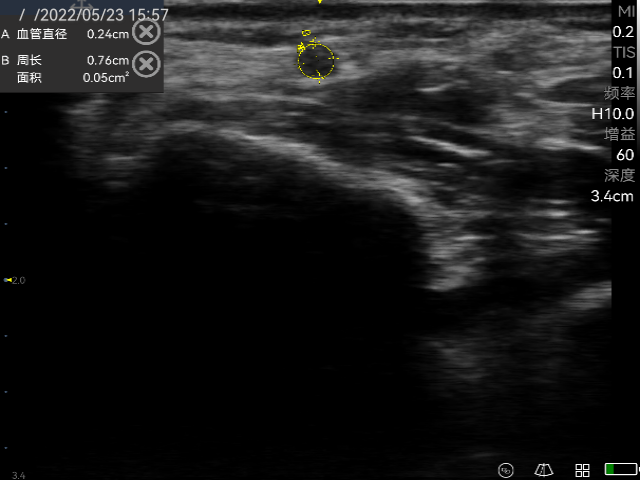

Accurate diagnosis of thyroid nodules and interventional guided puncture.

Breast and thyroid interventional ultrasound; Identify thyroid nodules and determine vascular lesions; Guide percutaneous biopsy to ensure accurate sampling; Guide fine needle aspiration to aspirate cysts.